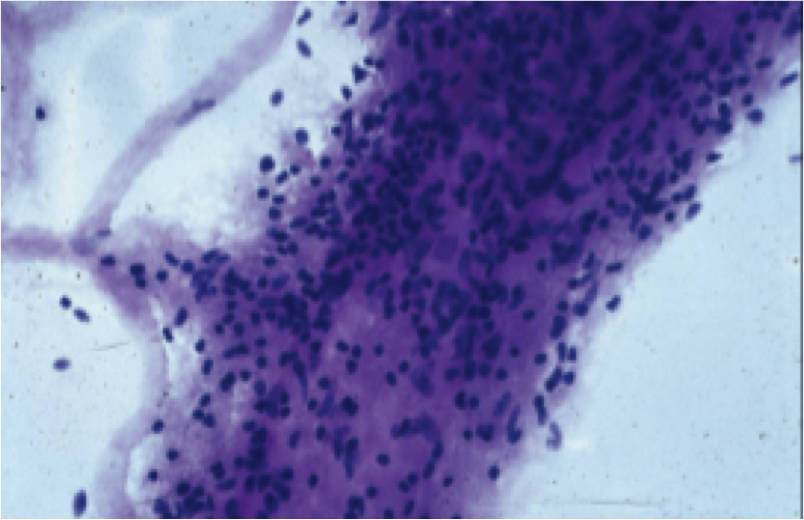

2020

Subretinal Drusenoid Deposit In Age-Related Macular Degeneration

This is a correlation with multi modal technology and clinical-pathological findings. It is the result of analysis of a post mortem eye with Age-Related Macular Degeneration, retrieved by the Eye Bank for Sight Restoration and studied by Macula Foundation investigators to interpret the nature of the images and provide a better understanding of the abnormalities to develop future forms of treatment.

Chen, L., Messinger, J. D., Zhang, Y., Spaide, R. F., Freund, K. B., Curcio, C. A., 2020. Subretinal drusenoid deposit in age-related macular degeneration: histologic insights into initiation, progression to atrophy, and imaging. Retina 40, 618-631. PMID 31599795